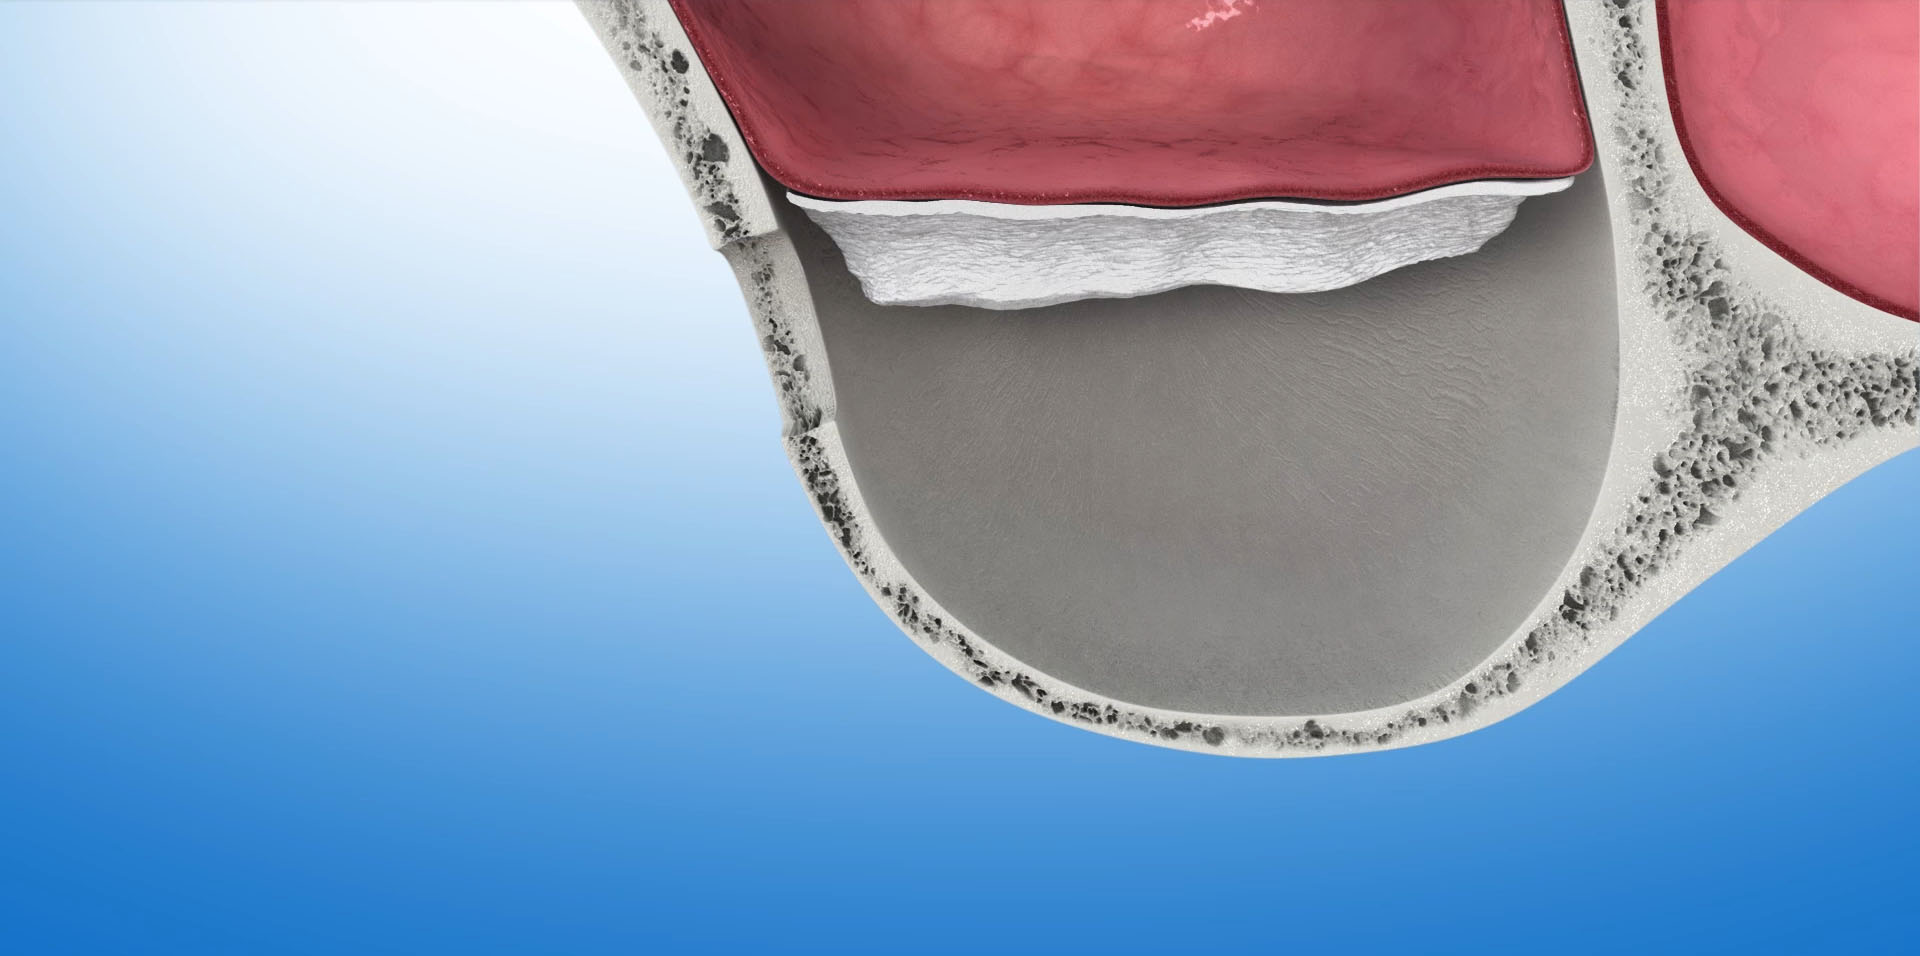

Zabiegiem operacyjnym, którego efektem jest odbudowa kości umożliwiająca implantację w tej okolicy szczęki jest- podniesienie dna zatoki szczękowej -sinus lift. Przeprowadzony po raz pierwszy w 1975 roku, dzisiaj jest bardzo bezpiecznym i przewidywalnym zabiegiem, dającym bardzo dobre wyniki w leczeniu implantologicznym. W zależności od stopnia zaniku tkanki kostnej, która znajduje się pomiędzy zatoką szczękową a jamą ustną zabieg podniesienia dna zatoki szczękowej wykonywany jest dwoma metodami: otwartą lub zamkniętą.

Podniesienie dna zatoki szczękowej metodą otwartą

Polega na wycięciu w bocznej ścianie zatoki małego okienka, przez które narzędziami ultradźwiękowymi i ręcznymi delikatnie odwarstwiamy błonę śluzową zatoki od kości dna zatoki. W uzyskaną przestrzeń aplikujemy materiał kościotwórczy. Okienko pokrywamy membraną zaporowa i zamykamy dostęp do zatoki. Tą metodą możemy uzyskać nawet ponad 10mm nowej kości, która umożliwi nam implantację w tym obszarze. Po zabiegu następuje okres regeneracji kości, w czasie którego wprowadzony biomateriał zamienia się w tkankę kostną. W zależności od ilości użytego biomateriału i stopnia podniesienia dna zatoki okres ten może trwać od 6 do 12 miesięcy.